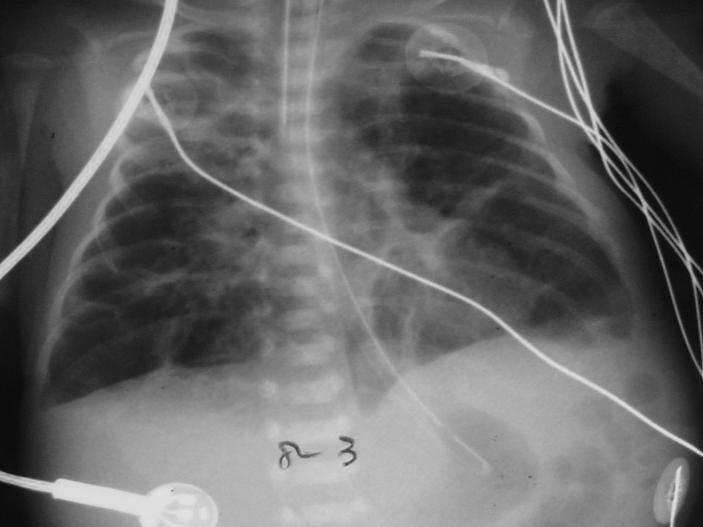

【109-1 醫學(四) 第74題】

下圖為一孩童之胸部X光素片,最可能的診斷為:

詳解

破題關鍵

這張胸部X光片顯示孩童雙側肺部有瀰漫性、不均勻的病變,包含粗糙的網狀陰影和囊狀透亮區,這些都是肺支氣管發育不良的典型影像特徵。

選項拆解

-A:錯在肺隔離症(pulmonary sequestration)通常表現為肺部一個界線清楚的實質性腫塊,而非瀰漫性的肺部病變。